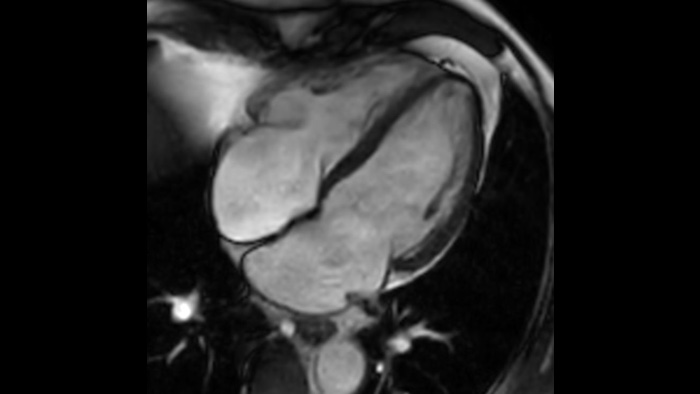

さらなる高速化の実現 MRI検査を最大65%高速化²、時間の有効活用が可能

検査ストレスからの開放 息止め時間を最大40%短縮、画像品質は実質的に同等³

確信が持てる画像診断 同じスキャン時間で、空間分解能を最大65%向上⁴

確信が持てる画像診断 すべての臨床領域でイメージング機能を拡張します。医療従事者が享受できるメリットをご覧ください。

1 稀なケースとして、マグネットの密封が損なわれた場合でもヘリウムの量はわずかであるため、漏れたヘリウムが室内の酸素レベルに影響を与えることは実質的にありません。 2 Philips SENSEとの比較。 3 心拍数が低い (50 bpm) とき。Compressed SENSEなしのフィリップススキャンと比較した場合。 4 等方性3D MSK VIEWスキャンで、Compressed SENSEなしのフィリップススキャンと比較した場合。